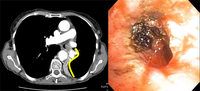

Золотистый-S или обратный S-знак на КТ грудной клетки (изображение слева), отмеченный желтой линией. Гибкая бронхоскопия (изображение справа) показывает центральное обструктивное поражение в левом главном бронхе.

Из коллекций Хосе Фернандо Сантакруза, дипломированного врача, члена Американской коллегии специалистов в области торакальной медицины, DAABIP, и Эрика Фолка, дипломированного врача, магистра наук; используется с разрешения